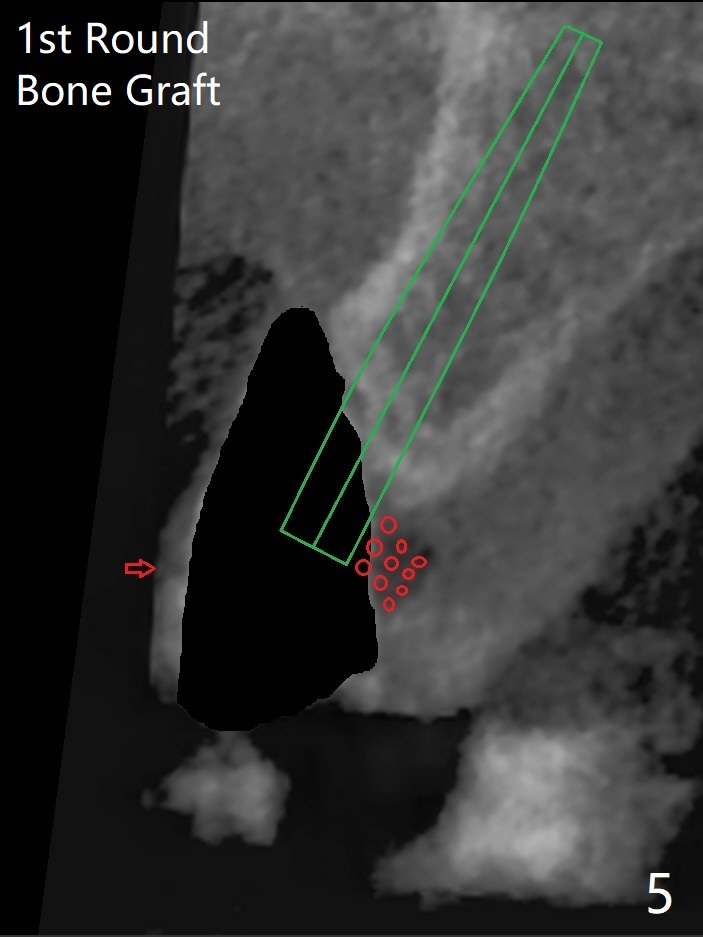

左上尖牙拔除前发现远中腭侧瘘道,拔除后发现相对牙槽嵴骨缺损(图一(术前CT):*),其实患牙根尖在颊侧骨板颊侧(图二:>),拔除后,根尖骨板缺损(图三:>),由于后者离颊侧牙槽嵴(图四:红箭头)远,骨粉修复重要性不如腭侧牙槽嵴(图四:白箭头),当窄植体植入后(图四:绿色),首先在腭侧植骨(图五:红圆圈),因为基台放置后(图六:粉红色),腭侧植骨开口狭窄(图六:白箭头)。即刻种植总是腭侧,颊侧间隙大,颊侧根尖缺损填骨应该容易(图七:橘黄色圆圈),即使不全(*),无关大局。徒手初步钻洞(图八),种植(图九)方向尚可,植骨好像完全(图十:*)。术后一周临时牙冠(11,尖牙)比侧切牙还短(图十一),随着愈合,尖牙牙冠会比双尖牙还短,因为植体偏腭侧,可能需要调整临时牙冠边缘。颊侧牙龈单纯疱疹感染,颊侧根尖仍有疼痛,腭侧瘘道缩小。